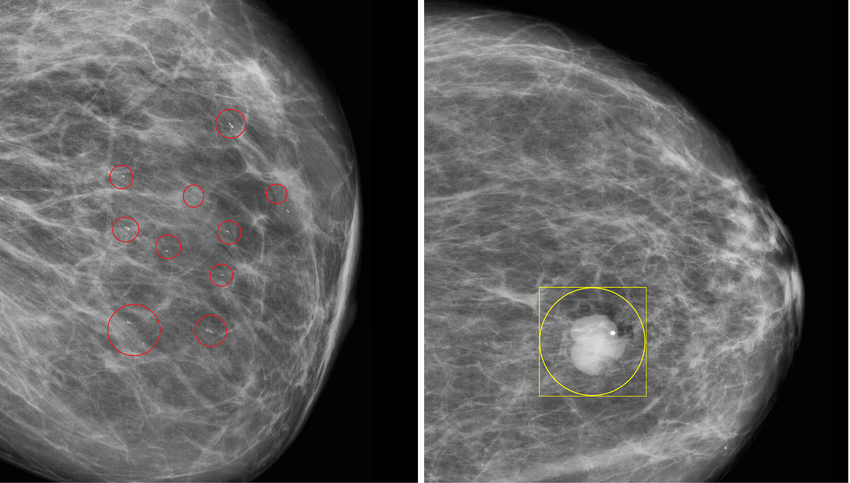

2. Automated CT Calcification Detection

Manual calcification review is slow, subjective, and clinically inconsistent. CtrlCV developed an AI-powered detection system that automatically identifies and measures both micro- and macro-calcifications, delivering consistent, objective, and rapid analysis. By converting a traditionally repetitive expert task into a reliable automated workflow, Koning benefits from faster reporting, reduced radiologist workload, and more standardised diagnostic outcomes which is a key advantages for clinical adoption and operational efficiency.